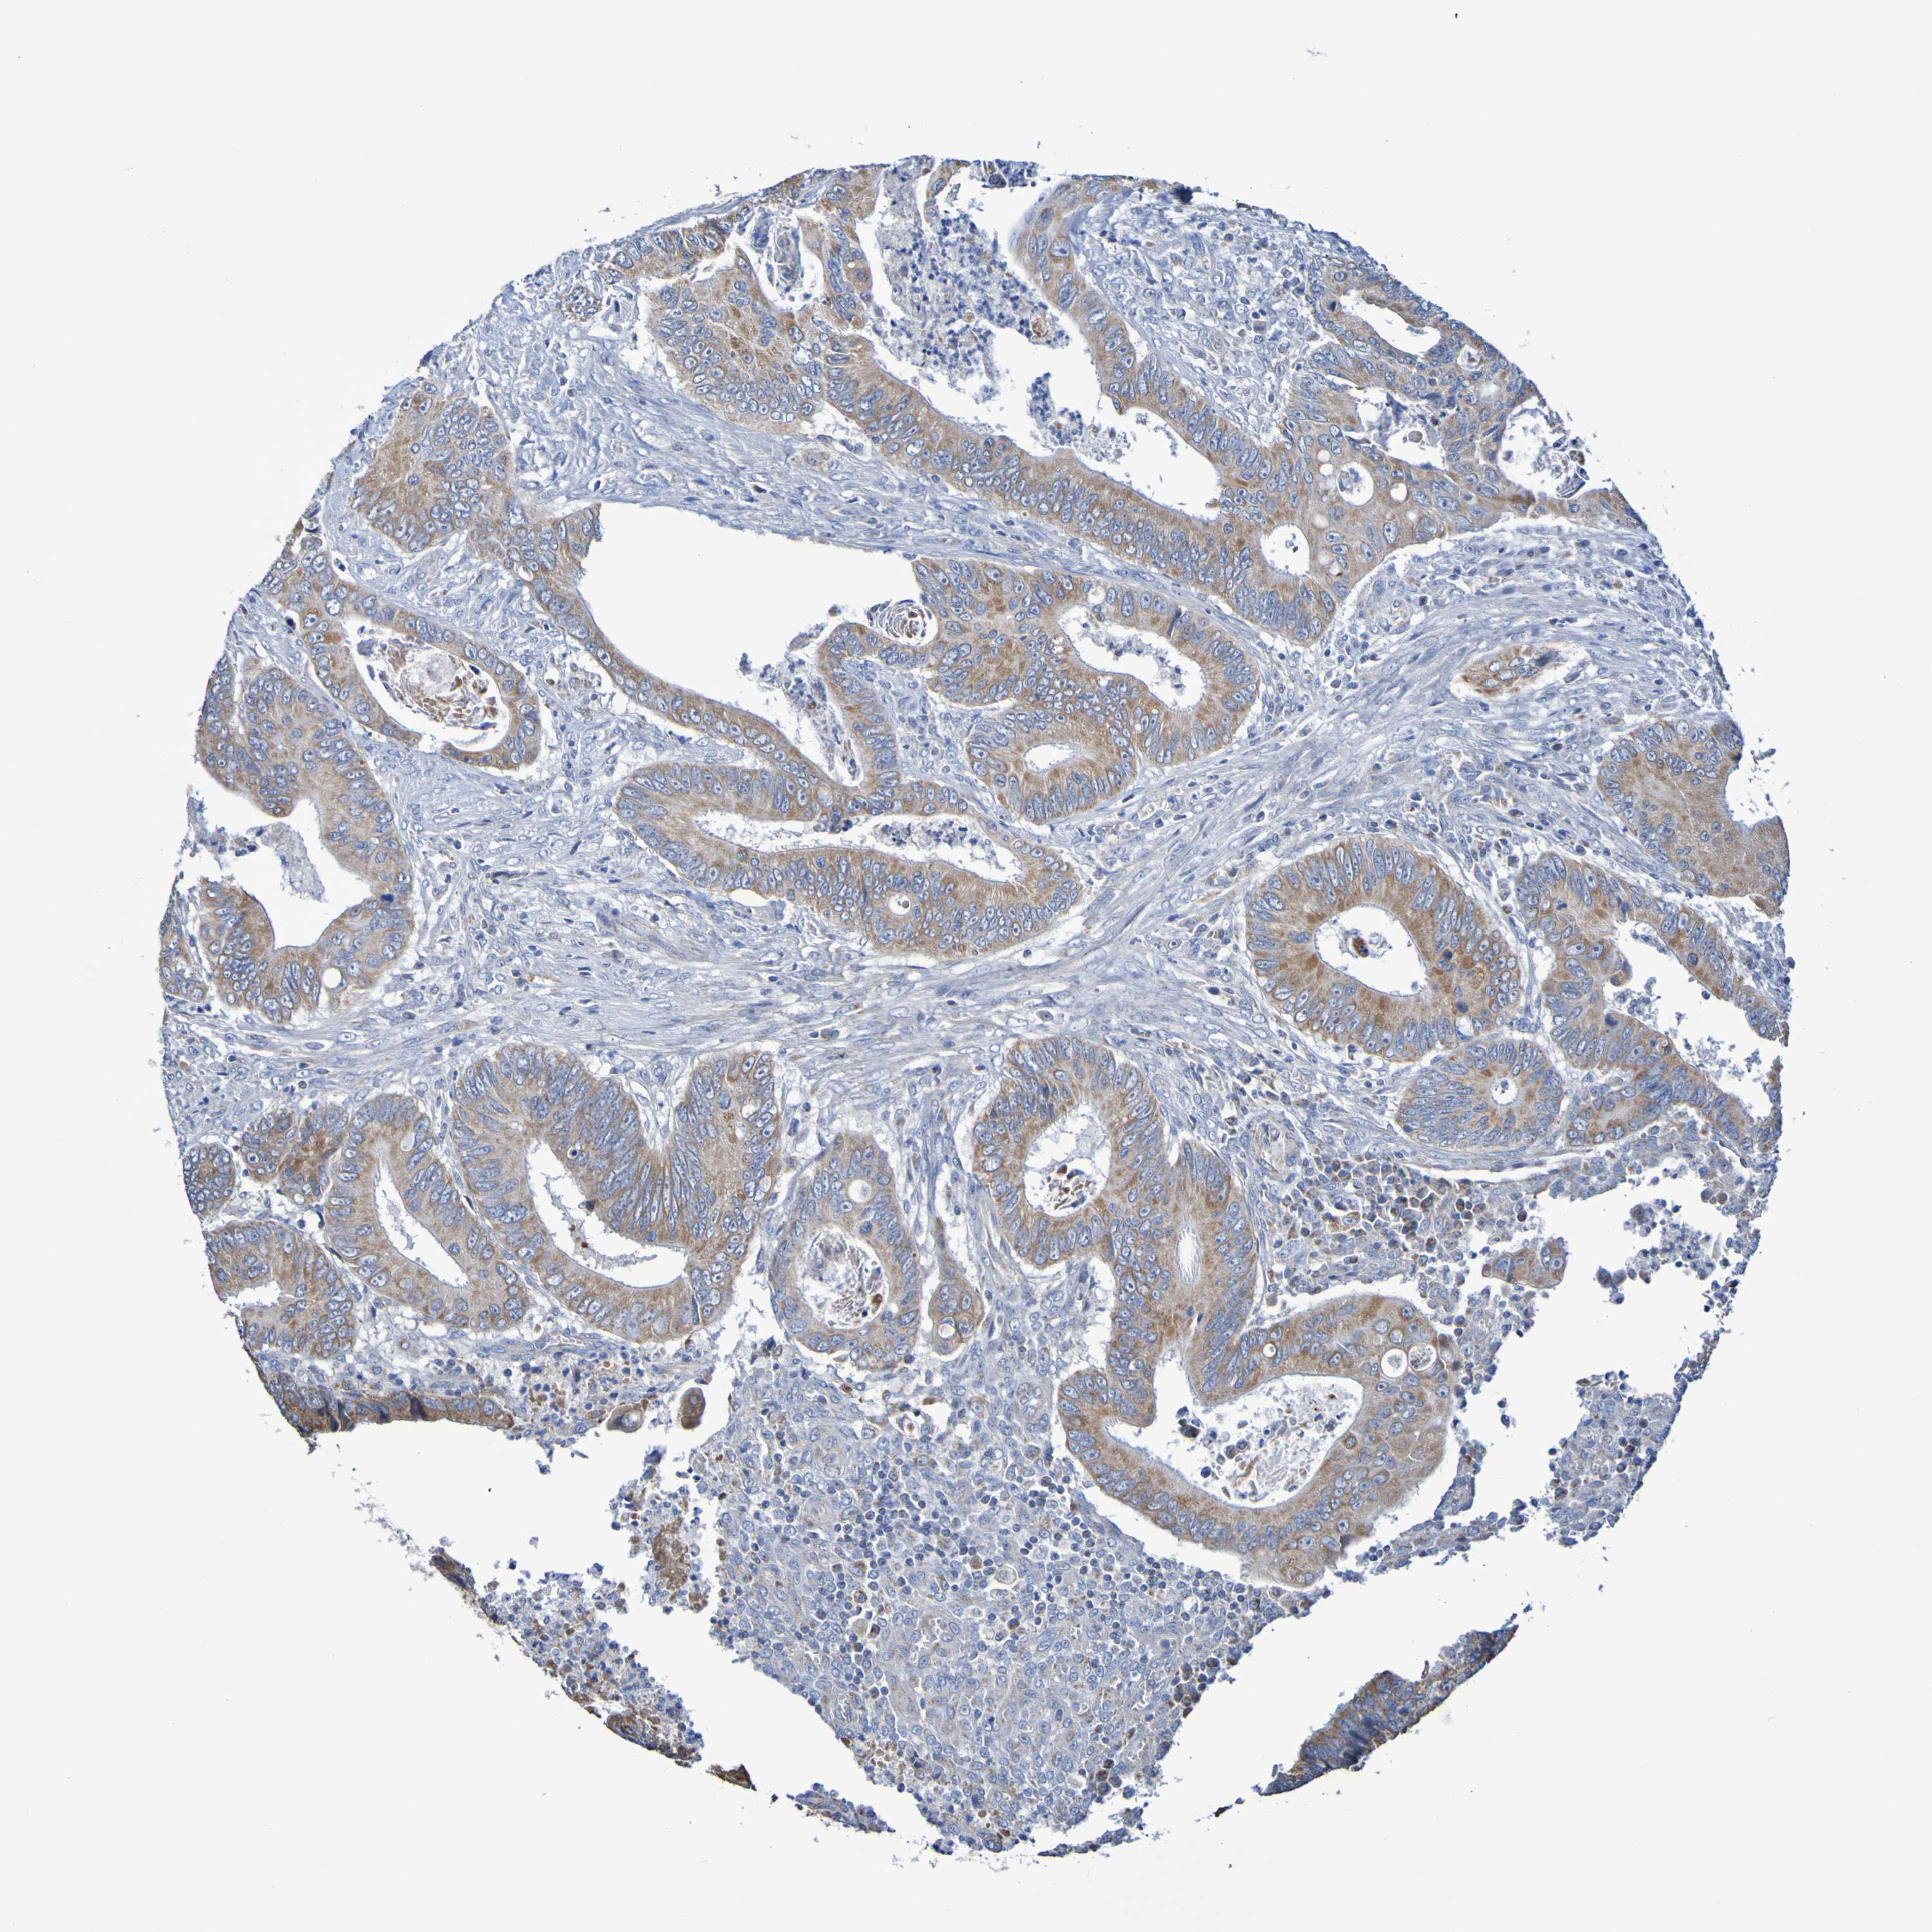

CANCER COLORECTAL CANCER Show tissue menu

Colorectal cancer

Human cancer

Colon adenocarcinoma